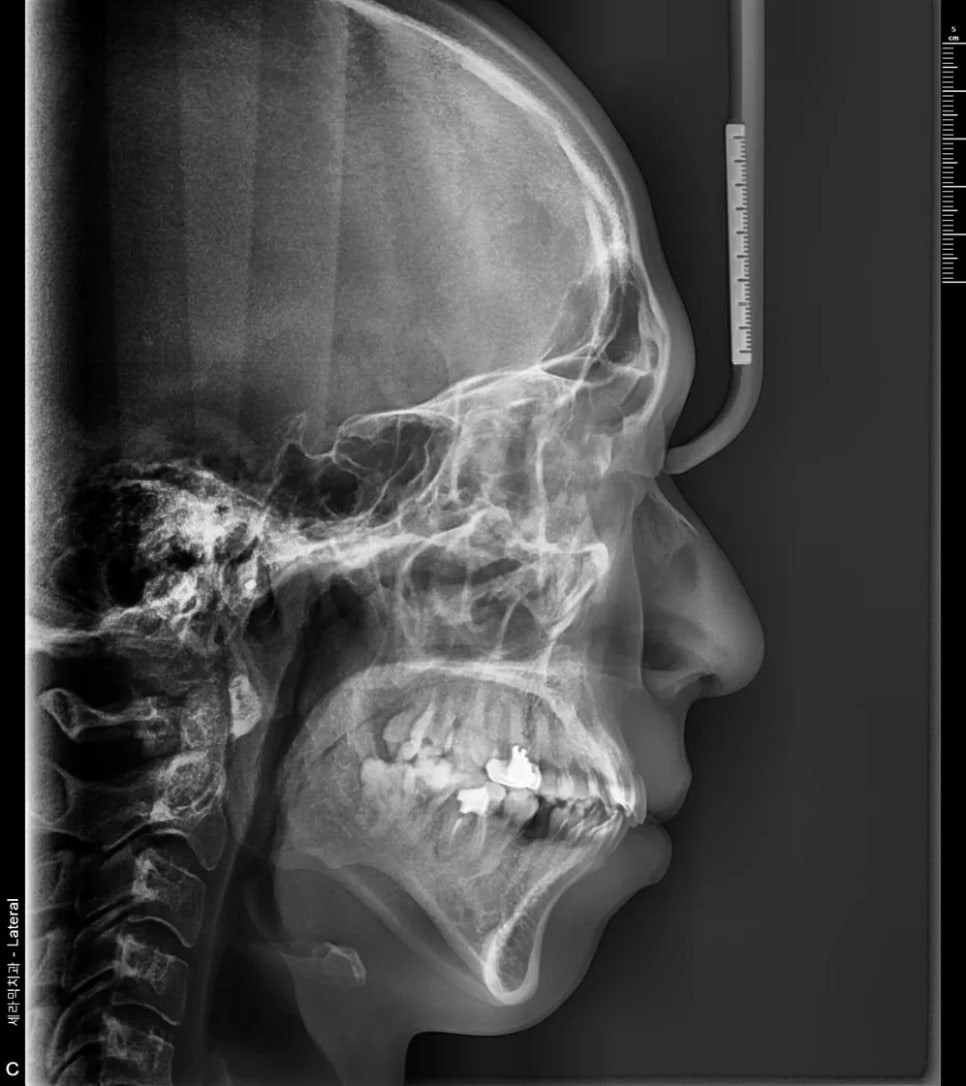

측면에서 확인한 돌출입 상태

그런데 정밀 분석(세팔로 분석)을 해보니, 흥미로운 점이 발견되었습니다. 돌출입이 맞긴 하지만, 아래턱 자체가 워낙 작은 편이라 돌출이 실제보다 더 강조되어 보이는 측면도 있었던 것입니다. 이런 부분은 정밀 검사를 하지 않으면 알기 어렵고, 치료 계획을 세울 때 매우 중요한 정보가 됩니다.

세팔로(측면 두부 방사선) 분석 – 돌출입이 맞지만, 작은 아래턱이 돌출을 더 강조하고 있습니다